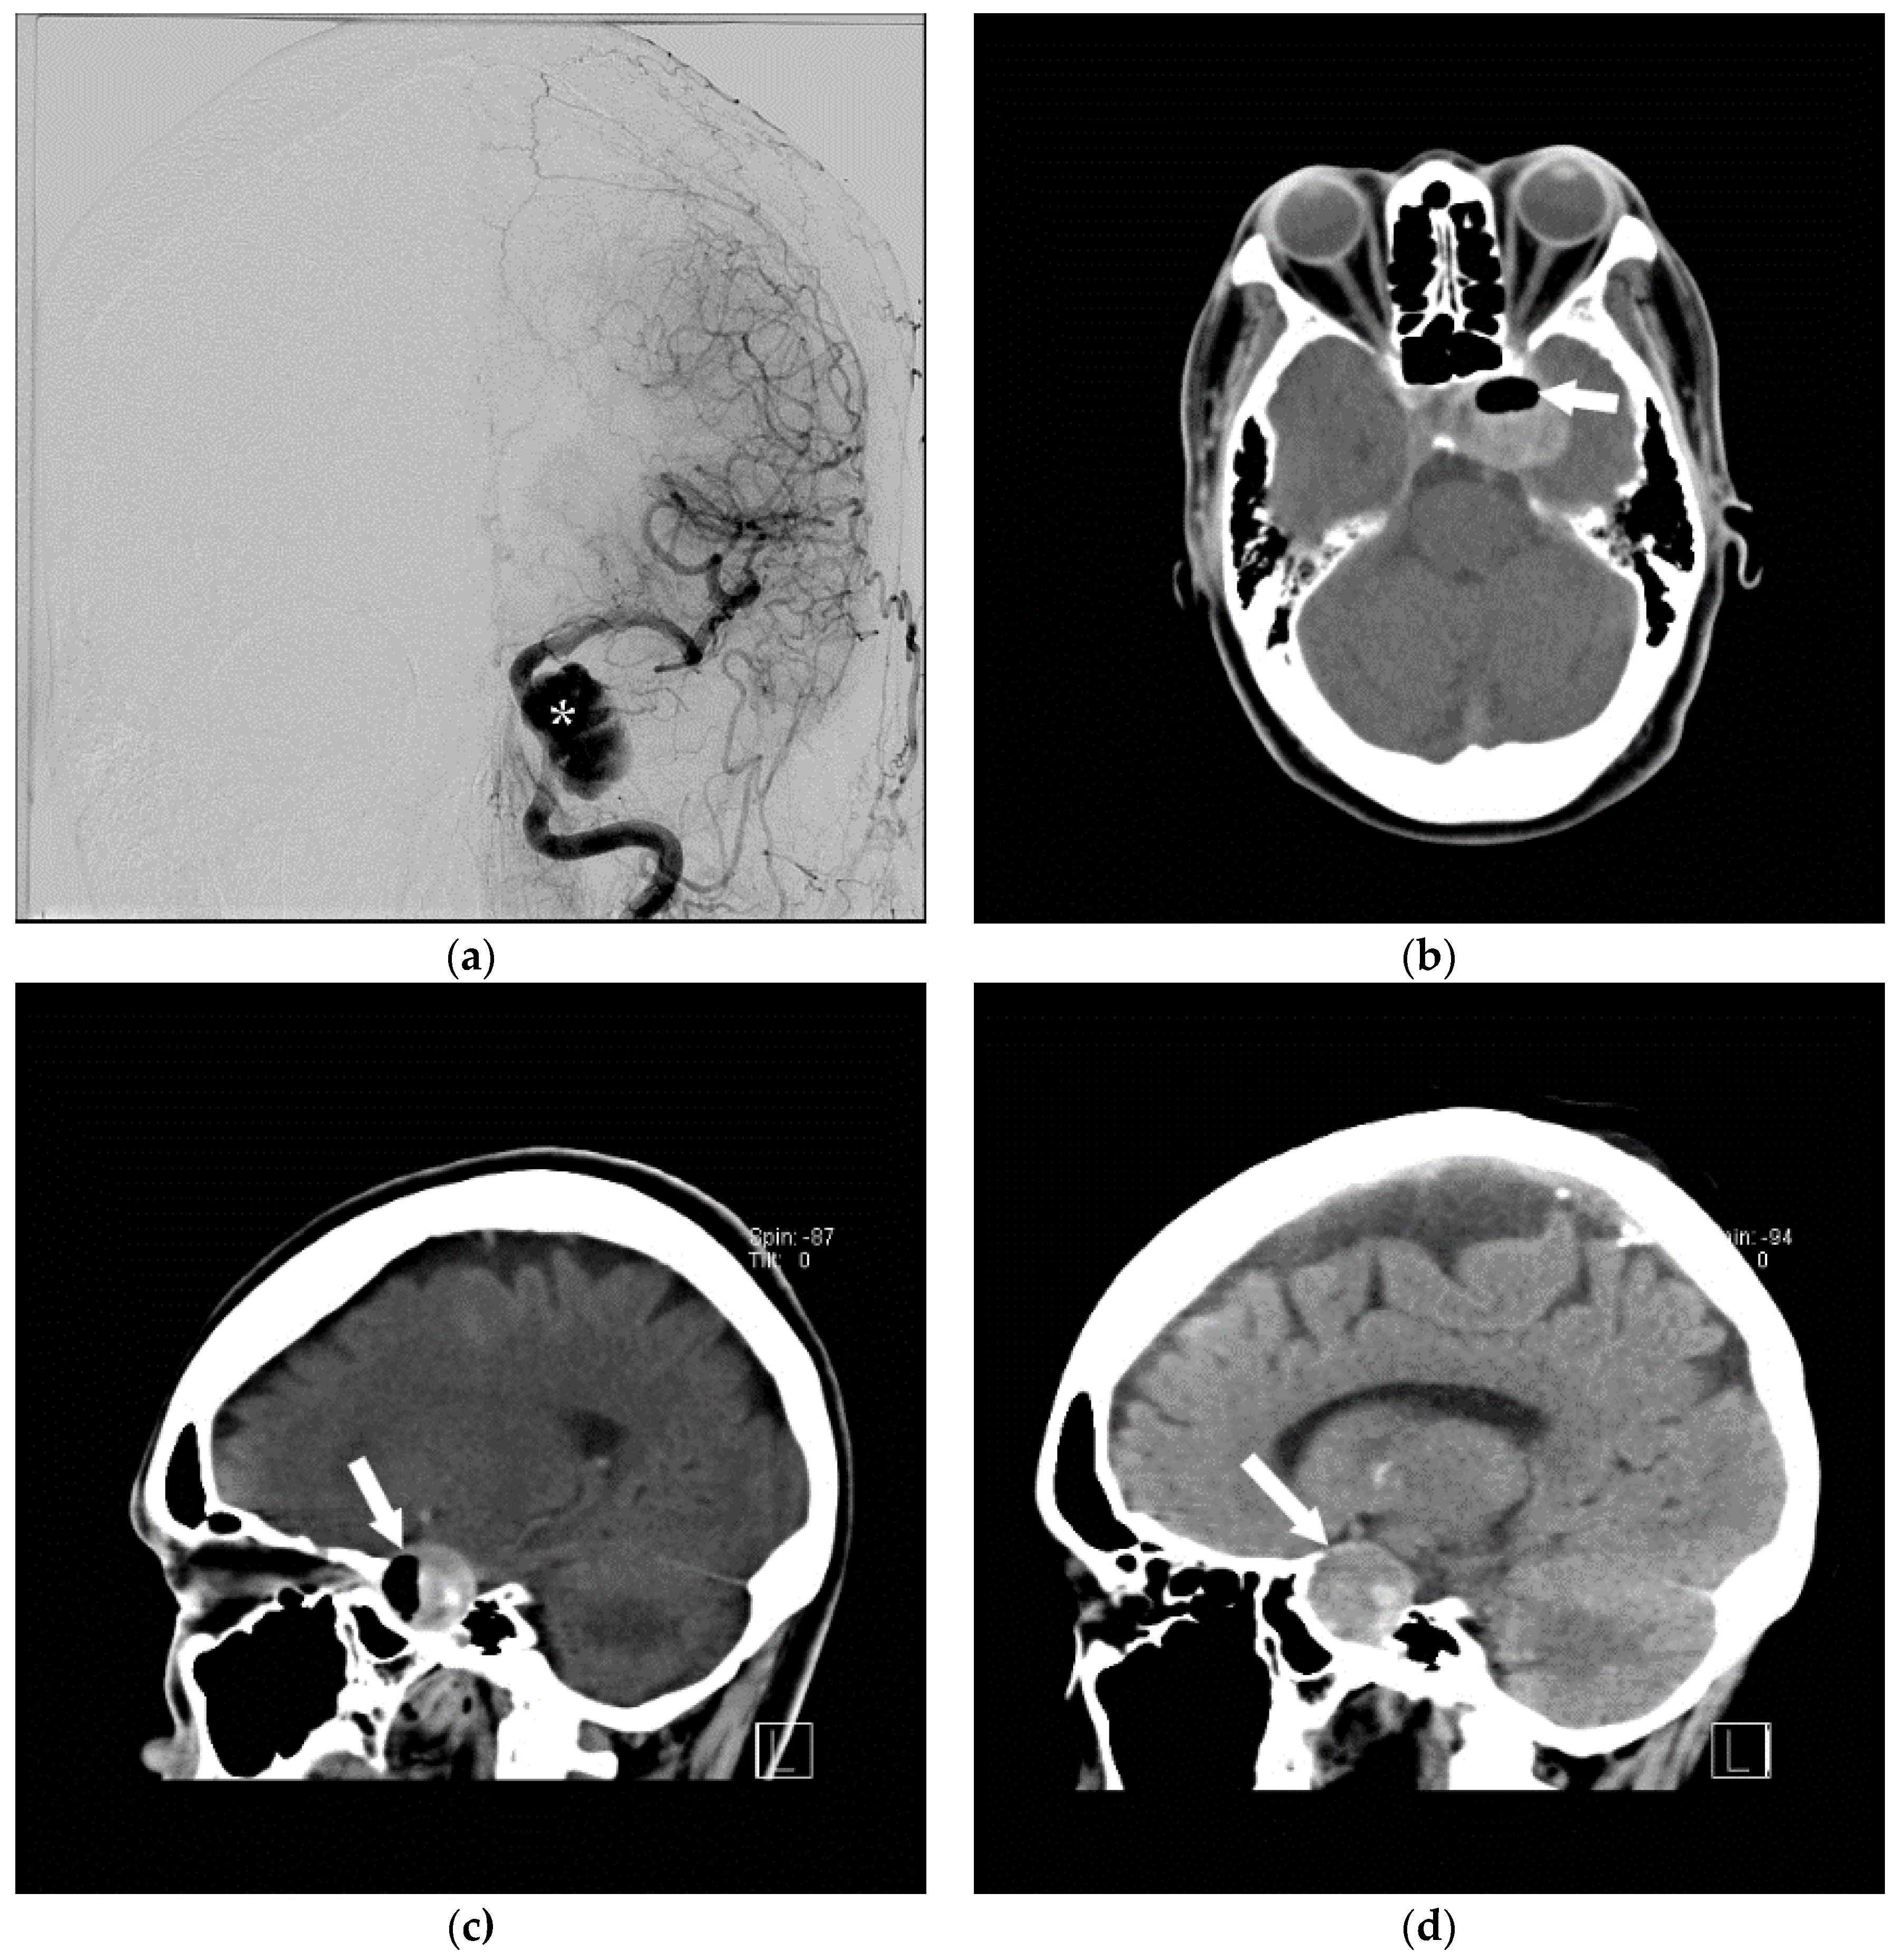

5. Air Embolism Management

5.2. Advanced Management

5.3. Air Aspiration